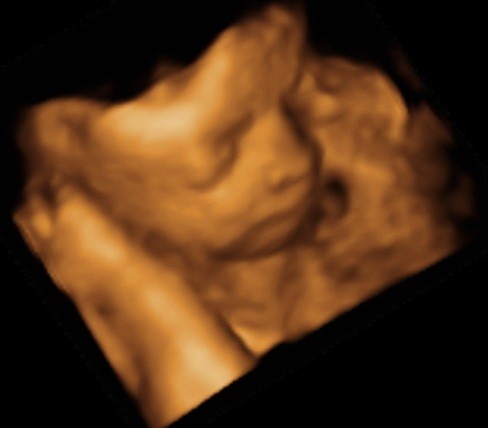

ślicznyNie wiem, ktory temat odpowiedni, wiec wstawie fotki naszego synka tutaj (nie sa to medyczne skany, wiec watek lekarski chyba nie pasuje, nie sa to tez zdjecia brzuszka...)

Zobacz załącznik 435458